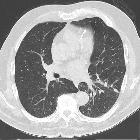

Lungenmetastasen Schilddrüsenkarzinom

Lungenmetastasen Radiopaedia • CC-by-nc-sa 3.0 • de

Pulmonary metastases typically appear as peripheral, rounded nodules of variable size, scattered throughout both lungs . Atypical features include consolidation, cavitation, calcification, hemorrhage, and secondary pneumothorax.

CT is excellent at visualizing pulmonary nodules. Typically, metastases appear of soft tissue attenuation, well circumscribed, rounded lesions, more often in the periphery of the lung. They are usually of variable size, a feature which is of some use in distinguishing them from a granuloma .